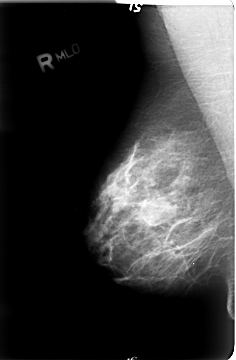

B_3023_1.RIGHT_MLO

RIGHT_MLO LINES 4680 PIXELS_PER_LINE 3064 BITS_PER_PIXEL 12 RESOLUTION 50 NON_OVERLAY